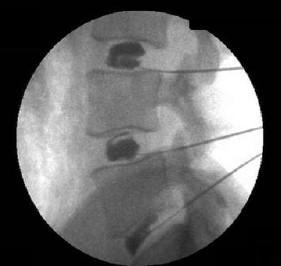

Nestes casos, com um auxílio de um catéter introduzido no espaço epidural guiado por uma agulha, injetamos solução salina em diversos pontos da coluna na tentativa de se desfazer as aderências epidurais, ao mesmo tempo promovendo redução do processo inflamatório, com injeção de corticosteróides, adiando ou evitando uma nova cirurgia. Este método, descrito pelo Dr. Gabor Racz, tem uma eficácia bastante promissora se realizado com a técnica correta.

Exemplo de adesiólise epidural realizada por via epidural caudal, no Hospital Abreu Sodré, a AACD.